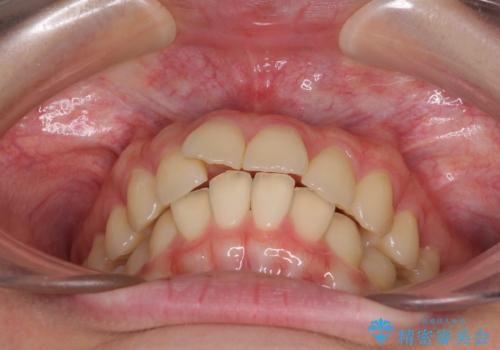

- 前歯2本が飛び出してることを気にして来院された患者様です。

全体的に黄ばんだ歯の色も気になるとのことで、マウスピース矯正により飛び出した前歯を治しつつ、ホームホワイトニングを併用して黄ばみを解消していくこととしました。

歯と歯の間を削ることで、飛び出した前歯が引っ込み、スッキリとした口元となりました。